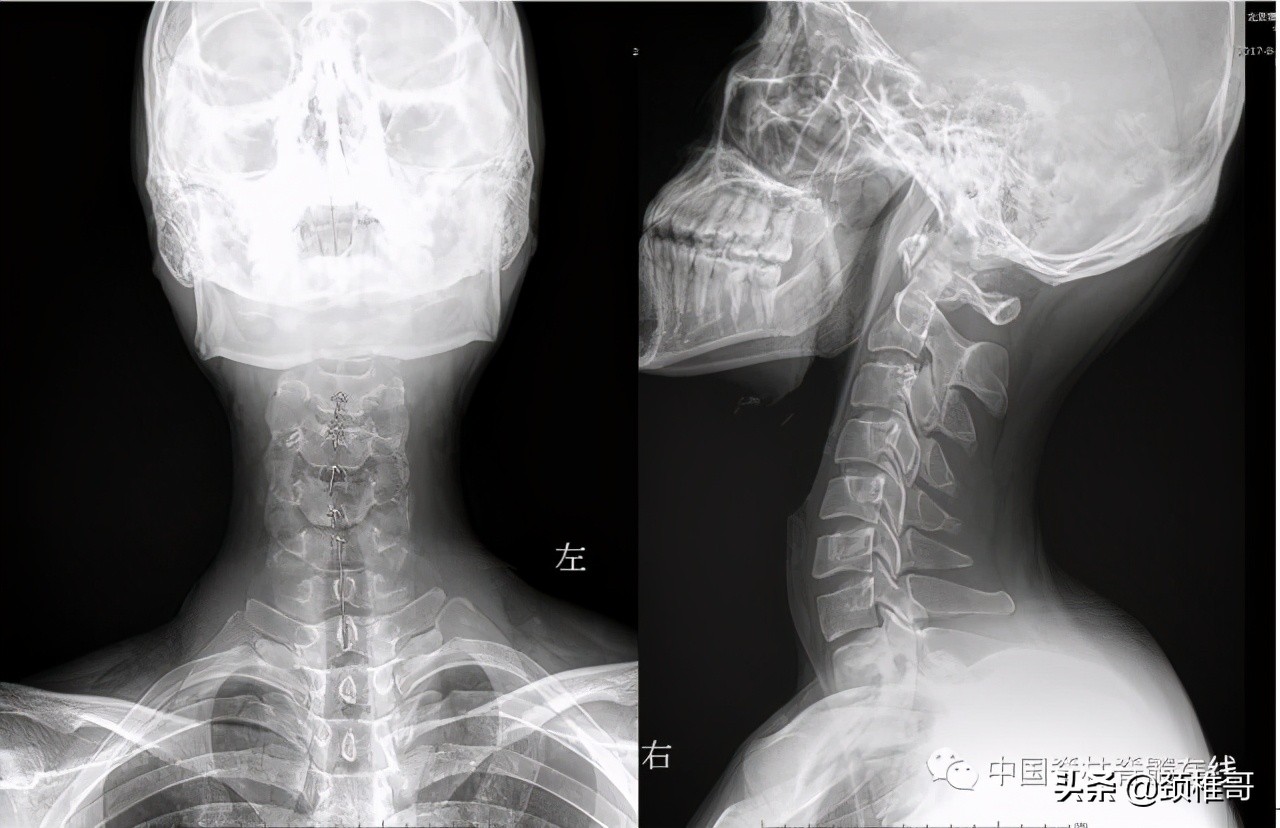

颈椎正侧位:序列 欠佳 动力位:颈椎3-6各个节段之间不稳

再看看这个病人,头晕2年,转头、低头时头晕加重,他的核磁共振显示椎间盘退变,水分减少了,但是没有明显的椎间盘突出,充其量算是膨出,但是我们看看他的x线片:颈椎3-5棘突序列不整齐,侧位显示颈椎5/6之间夹角增大,过伸位片显示,颈椎4-7各个节段夹角都超过了11°。过屈侧位片显示5、6、7三个节段出现了双边征,是椎体发生了旋转不稳的结果。这个病例的主要问题在于椎间盘吗?不对,在于肌肉和韧带对于颈椎4-7各个节段之间的稳定控制能力的减退。

正位:颈椎序列欠佳 侧位:颈椎4-7夹角增大

对节段颈椎成角过大、双边征